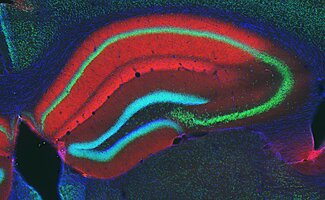

Cannabinoid Receptors

Cannabinoid receptors are transmembrane proteins that mediate the action of CBs.